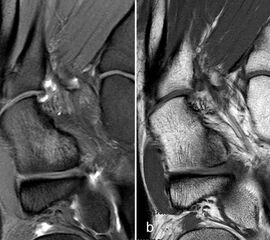

Der Begriff Morton-„Neurom“ ist im Grunde veraltet und irreführend, denn es handelt sich weder um einen Nerven- noch um einen Nervenscheidentumor, sondern um eine perineurale Fibrosierung. Da das interdigitale Gefäßnervenbündel charakteristisch in die Läsion hinein- und distal auch wieder aus der Läsion herauszieht, entsteht lediglich das Bild eines vom Nerven ausgehenden Tumors. Die charakteristischen Merkmale von Morton-„Neuromen“ sind deren Lage plantar auf Höhe der Metatarsaleköpfchen und die oft typische tropfenförmige Konfiguration (Abb. 10).

Aufgrund des hohen Bindegewebsanteils sind sie in der MRT in T2-gewichteten Bildern in der Regel auffallend signalarm, die T1 zeigt eine unspezifische Weichteilintensität. Die Anreicherung nach intravenöser Kontrastmittelgabe ist sehr variabel und erlaubt somit kaum diagnostische Rückschlüsse.

Durch seitliche Kompression des Fußes verlagern sich Morton-„Neurome“ oft weiter nach plantar in die Weichteile. Klinisch entspricht dies dem sogenannten Mulder-Zeichen 4. In der Bildgebung kann man sich den Effekt zu Nutzen machen, indem man in Bauchlage untersucht und durch die seitliche Fixierung eine entsprechende Kompression erzeugt. Die Befunde sind dann oft deutlich besser zu erkennen (Abb. 11).